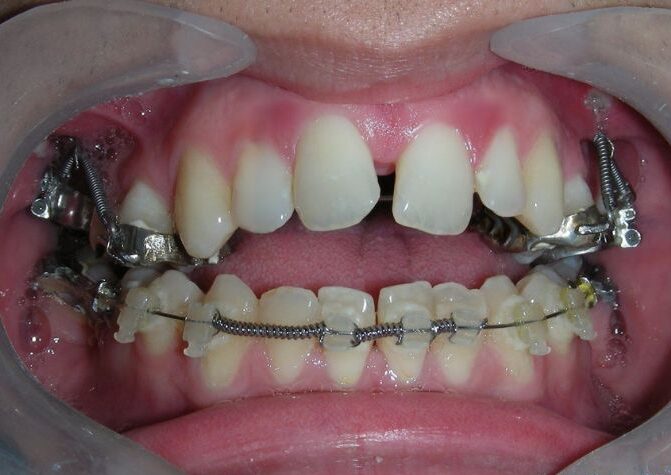

Was installed a Hyrax-type 10mm palatal expander of the Brazilian trademark Morelli® , modified by the author to be adapted to receive TADs microscrews, in order to initiate maxillary disjunction with MARPE (Mini-implant Assisted Rapid Palatal Expansion), TADS was installed with skeletal anchorage placed bilaterally having as references the roots of the maxillary canines and first premolars. Prior to insertion, local infiltrative anesthesia was administered using 2% lidocaine hydrochloride with 1:100,000 epinephrine. A total dose of approximately 0,8 mL per side (cortical infiltration technique). The TADs were inserted under aseptic conditions using a manual driver. Microscrew Evolution 1,6 Ø x 10 mm from the Argentine brand Odontit® . The Hyrax expander was then fitted and activated after 48 hrs .

Protocol of one activation per day was followed for a period of three weeks where the first clinical and radiographic evaluation was performed, showing clear signs of skeletal expansion, including the presence of a midline diastema. One more week of activations was added with a total of 28. The patient reported moderate headache during the first week of activation.

Having successfully achieved the expansion, we proceed to the intrusion of the posterior superior sectors, modifying the Hyrax by adding anchoring hooks at the buccal level of the first premolars. Using the Hyrax as anchorage, we sought a parallel intrusion. This could be replaced by a palatal bar. TADs were installed bilaterally at the mesial level of the first molars, inserting them as parallel as possible to the roots.

Simultaneously we begin with the alignment of the lower arch ,Simultaneously we began with the alignment of the lower arch with Roth prescription ceramic braces .022 . Henry Schein®

As the reader may infer, alignment and leveling of the upper anterior segment are being intentionally deferred at this stage of treatment. This strategic decision is based on the primary objective of closing the anterior open bite not through anterior extrusion, but by means of controlled posterior intrusion. This biomechanical approach promotes a counterclockwise rotation of the mandible, which leads to a increase in the facial axis angle and improvement in vertical facial proportions. By avoiding early anterior alignment, we prevent any premature vertical displacement of the upper incisors.